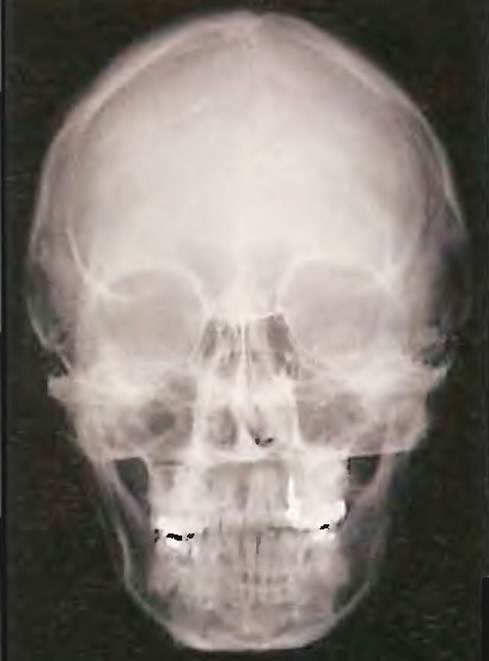

Анатомия детского черепа: Рентгеновские снимки и описание